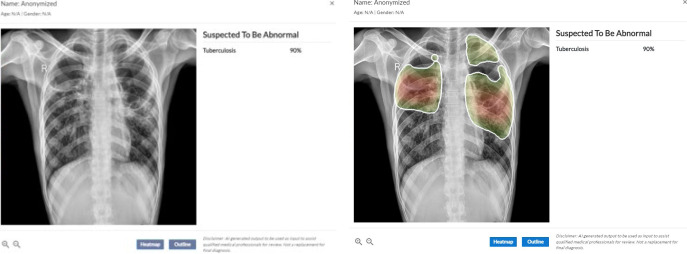

Materials and methods: Genki, an AI-based CADe software, was employed in four mobile diagnostic units in remote areas of Chennai, India for screening TB. Patients from remote areas of Chennai who visited the vans and registered in the screening program underwent chest radiography, and the acquired X-ray scans were analyzed using Genki, which provided an assessment of each scan as either "TB suggestive" or "TB not suggestive". Subsequently, sputum or swab from the patients with "TB suggestive" results was collected to confirm the diagnosis.